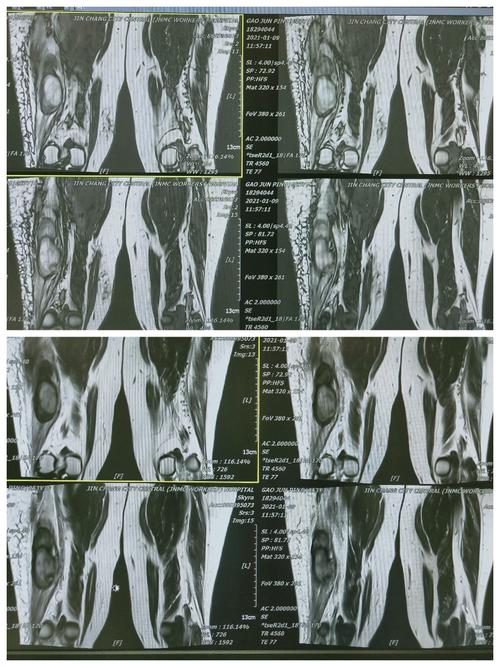

骨盆肌肉mri断层解剖

其它 下肢动脉瘤破裂出血 写美篇 彩超显示:右大腿外侧至膝关节处皮下